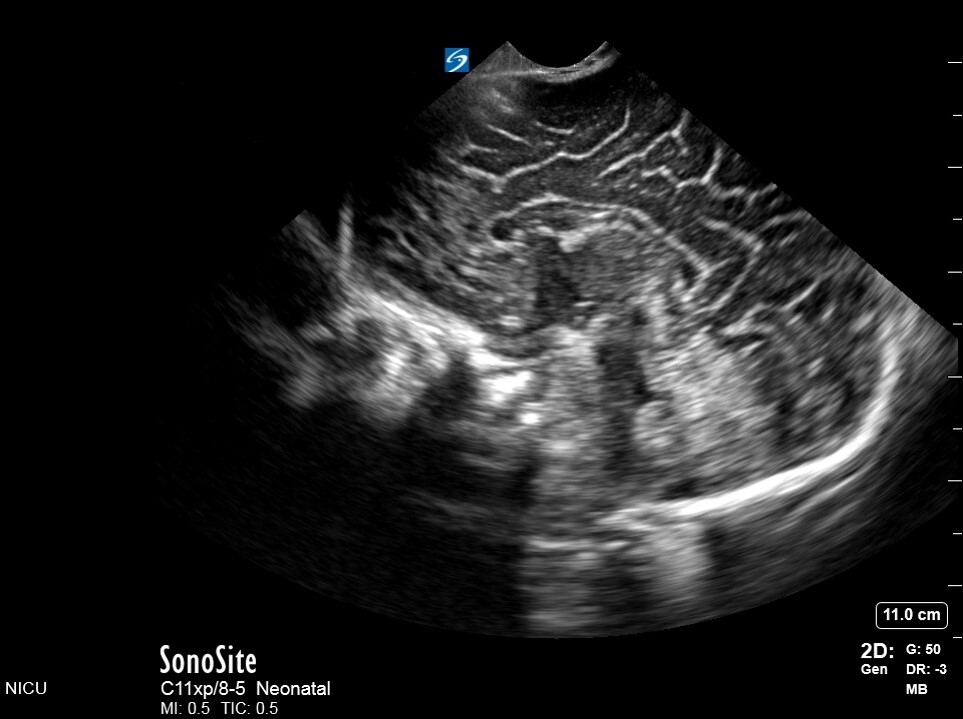

Neonatology S1 1 Image